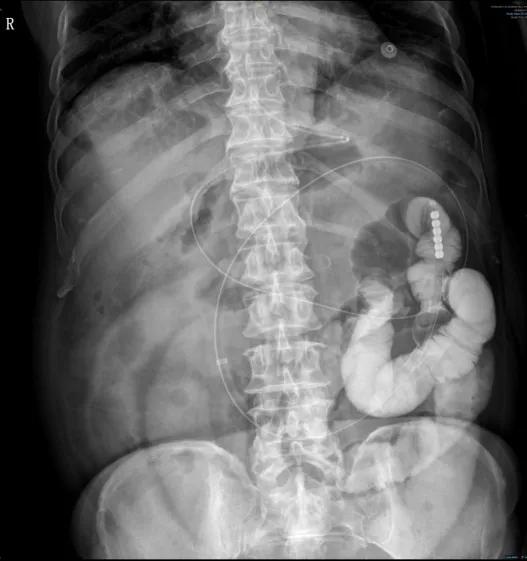

近期,昆山市一医院急诊外科连续收治了多位因吃柿子不当造成肠梗阻的老年人。

急诊外科常规开展经鼻肠梗阻导管置入术,术后患者胃肠道水肿明显消退,腹胀、腹痛减轻,肠道功能恢复的更快,能够及时缓解患者肠梗阻的症状,为肠梗阻患者提供了更优质的治疗。